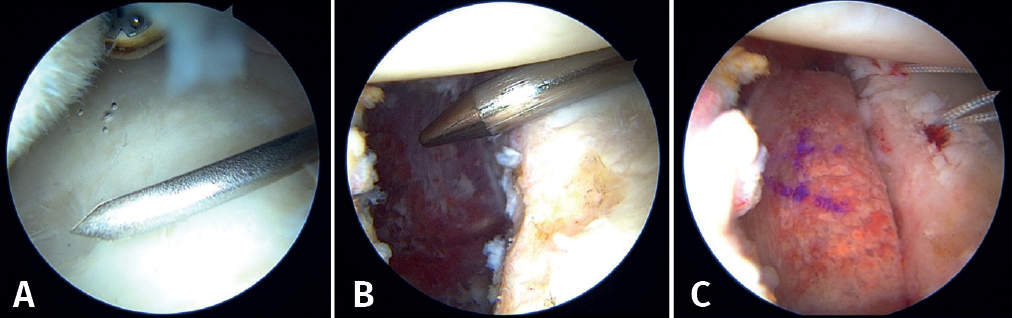

The patient is repositioned in lateral decubitus. Before placing the fields, a physical examination is performed to check glenohumeral instability with the modified anterior and posterior drawer tests(15). The humeral head is shown to engage in the glenoid with the arm in abduction and external rotation(6)(Video 1). Longitudinal traction is applied to the limb to be operated upon, according to the standard arthroscopy procedure. Arthroscopy is started through the posterior portal. An initial assessment of the location and extent of the lesions is made (Figure 2); the anterior portal is established under direct vision with the aid of a needle, 1-2 cm inferomedial to the anterolateral corner of the acromion, to penetrate within the rotator interval. An anterosuperior portal and a posteroinferior auxiliary portal are also established using an outside-in technique 2-3 cm below the posterior portal(16).

First, the glenoid is debrided with the aid of a shaver-type motor, and free bodies and bony debris are removed. The labrum and capsule are detached together from the glenoid margin, creating a wide recess to accommodate the graft, and the surface is prepared by creating bleeding edges with a burr. Then, using a posteroinferior auxiliary portal established under direct vision (Figure 3A), remplissage is started with debridement of the Hill-Sachs lesion and the placement of two bone implants - in this case HealicoilRegenesorb® (Smith & Nephew Inc., Andover, MA, USA) 4.5 mm double suture Ultrabraid® N.2 (Smith & Nephew Inc., Andover, MA, USA ) (Figures 3B and 3C). The 8 extremities are retrieved, passing them through the capsule approximately 1 cm apart and using a Sling-Shot® device (Stryker) (Figures 3D, 3E and 3F). The extremities are left untied in the posterior portal.